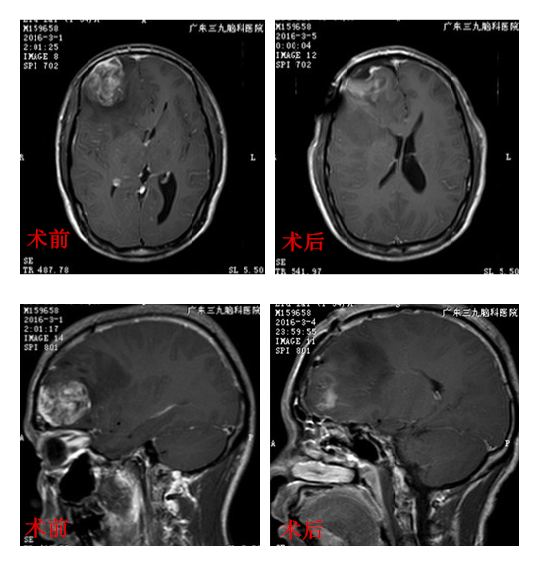

求治广东三九脑科医院,神经外三科杨宝应主任阅片后解析:患者颅内占位巨大,目前已出现反复头痛,颅脑MRI检查提示占位效应明显,已形成脑疝,需进行手术治疗来解除颅内高压。

完善术前相关准备,2016年3月3日由杨宝应主任主刀在全麻下为其进行“右额占位性病变切除术+ICP探头置入术”。手术顺利,术后刘先生神志逐渐清醒,并辅以放疗治疗。出院时,刘先生头痛症状消失,对答切题,四肢可自主活动。